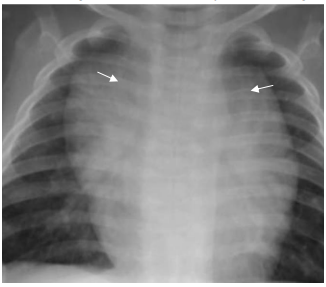

Observe a radiografia de tórax de uma criança de 4 meses a seguir:

Em relação à imagem, é correto afirmar que

As setas indicam

Provas